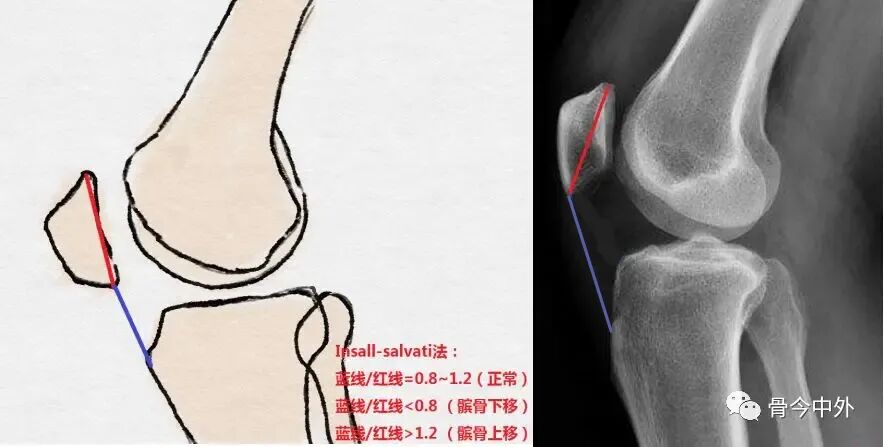

髌骨高度

最常用的三种测量方法:

Insall-Salvati

-髌骨下极至胫骨结节顶点上缘(蓝线)

-髌骨最长对角线的长度(红线)

判断标准:

指数 | 正常范围 | 高位髌骨 | 低位髌骨 |

Insall-Salvati index | 1 | >1.2 | <0.8 |

Modified Insall-Salvati | 1.25 | >2.0 | |

Caton-Deschamps Index | 1 | >1.3 | <0.6 |

Blackburn-Peel Index | 0.6 | >1.0 | <0.8 |

Insall-Salvati指数测量法:髌腱长度/髌骨最长对角线的长度,即LP/LT;

Modified Insall-Salvati index为改良Insall-Salvati指数。